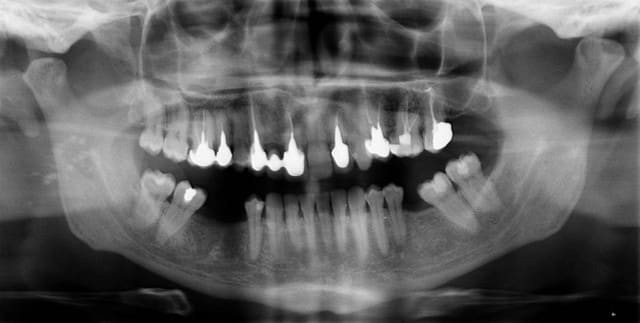

Que pensez-vous des ces petites taches au niveau de la branche montante droite de ce patient de 40 ans :

- des calculs parotidiens ?

- des nodules cancéreux ??

- de l'acné caché ;-) ? il n'y a rien de particulier sur la peau

- des plombs de chasse ;-) ? (je sais c'est pas assez radio-opaque)

- ??

Il n'y a aucun symptôme particulier, le patient ne se plaint pas de cet endroit, c'est en prenant une pano "de dépistage" que j'ai vu ça. Il est non fumeur, pas de problème de santé à signaler.

Calculs parotidiens

Calculs

Oui, enfin des calculs quoi.

Attention verifie que ton patient n'a pas eu dans le passé de tuberculose.

Elle peut entrainer apres plusieurs années des calcifications ganglionnaires...

Calculus parotidiens.Mais il faut toujours penser a un proces neoplastique.